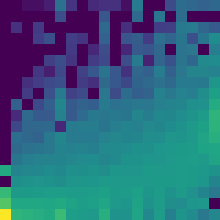

Data augmentation has been widely used for training deep learning systems for medical image segmentation and plays an important role in obtaining robust and transformation-invariant predictions. However, it has seldom been used at test time for segmentation and not been formulated in a consistent mathematical framework. In this paper, we first propose a theoretical formulation of test-time augmentation for deep learning in image recognition, where the prediction is obtained through estimating its expectation by Monte Carlo simulation with prior distributions of parameters in an image acquisition model that involves image transformations and noise. We then propose a novel uncertainty estimation method based on the formulated test-time augmentation. Experiments with segmentation of fetal brains and brain tumors from 2D and 3D Magnetic Resonance Images (MRI) showed that 1) our test-time augmentation outperforms a single-prediction baseline and dropout-based multiple predictions, and 2) it provides a better uncertainty estimation than calculating the model-based uncertainty alone and helps to reduce overconfident incorrect predictions.